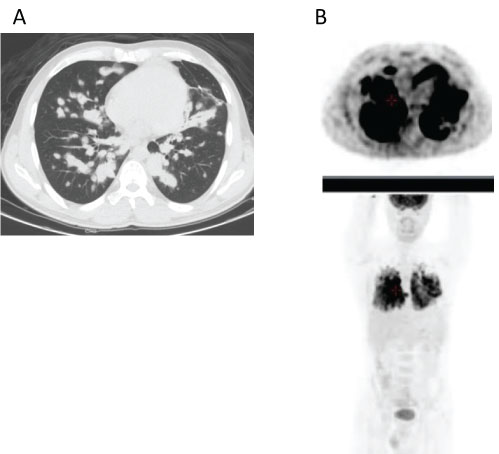

A 32-year-old man was referred to our institution in November 2015 because of appearance of several, progressive, neurological symptoms within a period of weeks: headaches, slight left hemiparesis and mild cognitive impairment. Since October 2014, he was followed in another institution for lung lymphoid granulomatosis, grade 2 (lung biopsy displays 18% EBV- positive cells using FISH analysis). FDG PET-CT (whole body scan without study of the brain), performed on 31/01/2015 showed a nodular infiltration of both lungs with an intensive bilateral lung uptake of FDG tracer (Figure 1A and Figure 1B). Due to absence of clinical symptoms he did not received any specific treatment and was followed clinically and radiographically with subsequent spontaneous resolution of lung lesions.

Figure 1: CT scan performed on 31/01/2015 demonstrated nodular infiltration of both lungs (Figure 1A) with a high uptake of FDG tracer on PET imaging (Figure 1B). View Figure 1